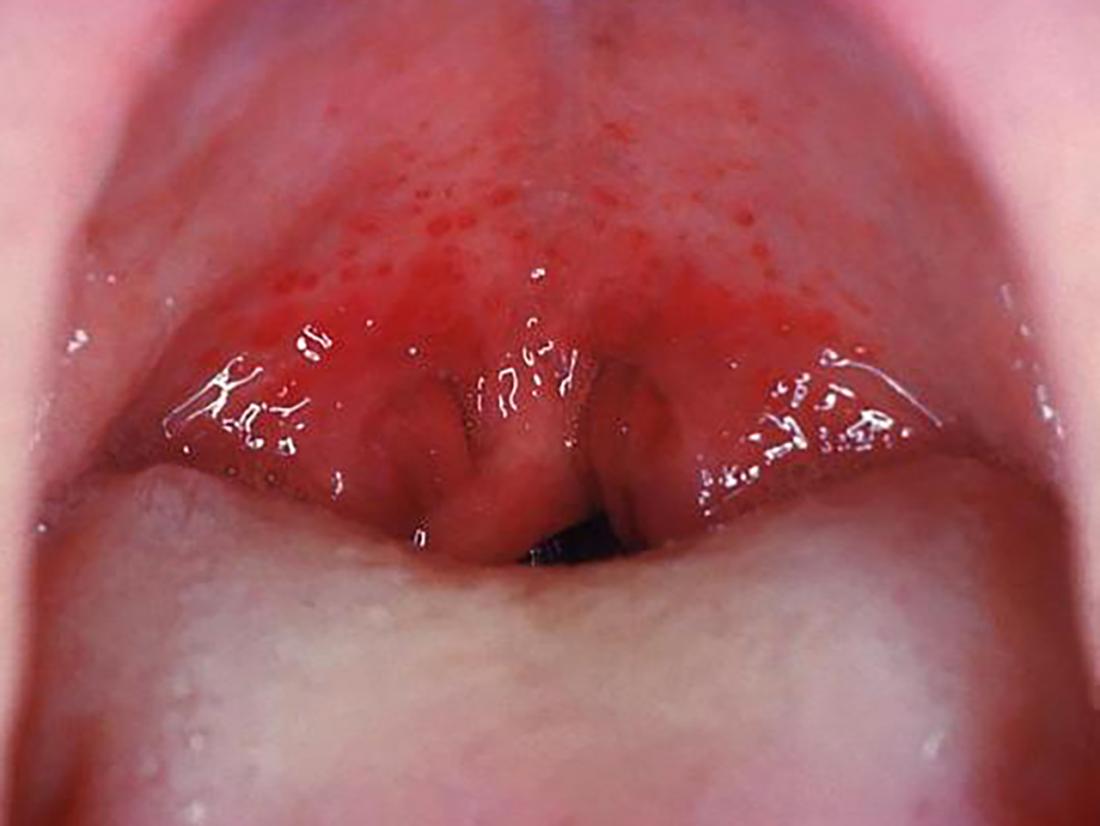

Las infecciones virales, como el resfriado común y la gripe, son causas frecuentes de irritación de garganta, a menudo acompañada de tos y congestión nasal. La infección viral causa inflamación de las vías respiratorias, produciendo irritacion de garganta y tos seca. La faringitis estreptocócica, una infección bacteriana, causa una garganta muy irritada, con frecuencia acompañada de fiebre, dolor de cabeza, y malestar general. La tos seca picor garganta puede también estar presente en este caso. El diagnóstico diferencial entre las infecciones virales y bacterianas es esencial para determinar el tratamiento adecuado.

Las infecciones bacterianas requieren tratamiento con antibióticos para prevenir complicaciones. En el caso de la faringitis estreptocócica, el tratamiento con antibióticos es crucial para prevenir la aparición de fiebre reumática, una complicación potencialmente grave. Las infecciones virales, por otro lado, por lo general, se resuelven por sí solas en unos pocos días, aunque los síntomas pueden tratarse para aliviar la incomodidad. Es importante recordar que el uso inapropiado de antibióticos puede contribuir al desarrollo de resistencia a los antibióticos.

El diagnóstico de las infecciones de garganta se basa en la evaluación clínica del paciente, incluyendo la observación de la garganta, y la historia de los síntomas. En algunos casos, se puede realizar un cultivo de garganta para identificar el agente infeccioso y determinar el tratamiento más adecuado. La prevención de infecciones respiratorias se basa en medidas de higiene como el lavado de manos frecuente, la vacunación contra la gripe y la neumonía, y evitar el contacto cercano con personas enfermas. Un descanso adecuado y una hidratación suficiente también son importantes para facilitar la recuperación.